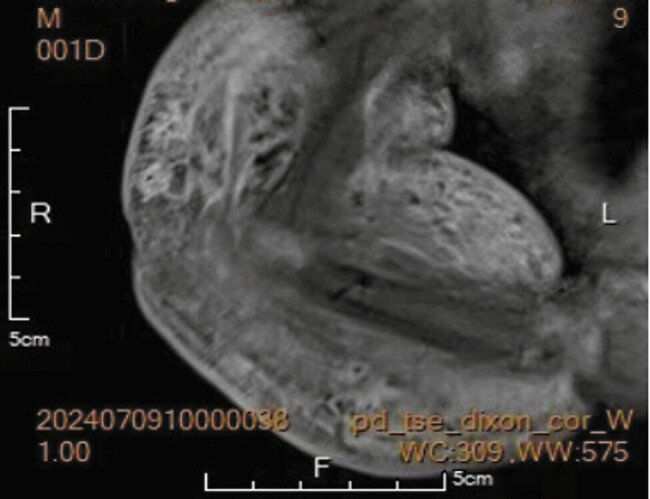

Methods: A full-term male neonate with prenatal right upper limb thickening presented postnatally with a violaceous, firm mass. Laboratory findings confirmed KMP. Due to recent BCG vaccination, sirolimus was initially withheld. First-line therapies failed, prompting sirolimus initiation on day 3, supplemented by fibrinogen transfusions.

Results: Platelets normalized by day 13 (283 × 10 9 /L) with marked tumor regression. Transient fever/diarrhea resolved with supportive care. At discharge (day 27), platelets stabilized (183 × 10 9 /L). Three-month follow-up showed sustained platelet recovery (268-532 × 10 9 /L), near-complete tumor resolution, and age-appropriate development. Prophylactic trimethoprim-sulfamethoxazole prevented infections.